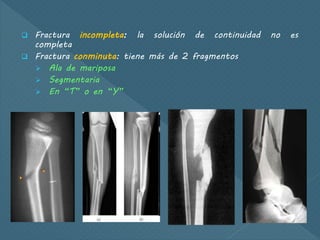

 Fractura incompleta: la solución de continuidad no es

completa

 Fractura conminuta: tiene más de 2 fragmentos

 Ala de mariposa

 Segmentaria

 En “T” o en “Y”

 Fractura incompleta:la solución de continuidad no es completa  Fractura conminuta: tiene más de 2 fragmentos  Ala de mariposa  Segmentaria  En “T” o en “Y”